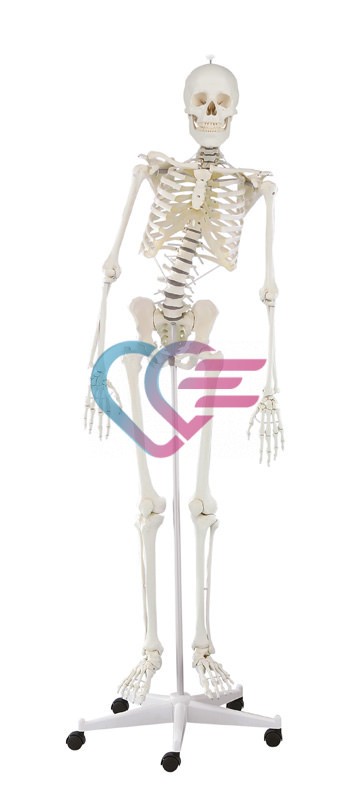

- Prvoklasni odljev kostura djeteta starosti 14 do 16 mjeseci.

- Prikazuje nesrasle epifize dugih kostiju i hrskavične rubove mnogih kostiju što je tipično za ovo doba razvoja.

- Sve fisure i otvori su pažljivo reproducirani.

- Udovi su ograničeno pokretljivi.

- Visina: 65 cm.

- Isporučuje se sa stalkom.

KOSTUR (SKELET) DJETETA STAROSTI 14 DO 16 MJESECI

ŠIFRA: KOSTU0010

- Prvoklasni odljev kostura djeteta starosti 14 do 16 mjeseci.

- Prikazuje nesrasle epifize dugih kostiju i hrskavične rubove mnogih kostiju što je tipično za ovo doba razvoja.

- Sve fisure i otvori su pažljivo reproducirani.

- Udovi su ograničeno pokretljivi.

- Visina: 65 cm.

- Isporučuje se sa stalkom.